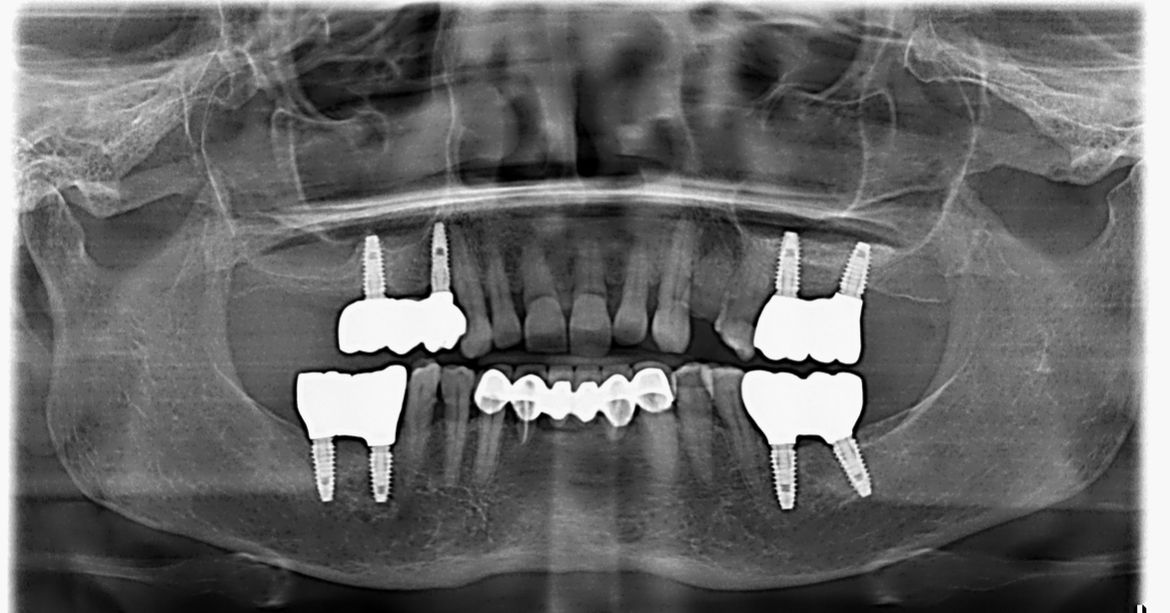

Dental Implant Surgery is a modern, permanent solution for replacing missing teeth using titanium implants that act as artificial tooth roots. These implants fuse naturally with the jawbone, providing exceptional stability and support for crowns, bridges, or dentures. The procedure restores full chewing ability, enhances smile aesthetics, prevents bone loss, and offers a long-lasting, natural-feeling replacement that looks, feels, and functions just like real teeth. With advanced techniques and precise planning, dental implants deliver reliable, comfortable, and life-changing results.